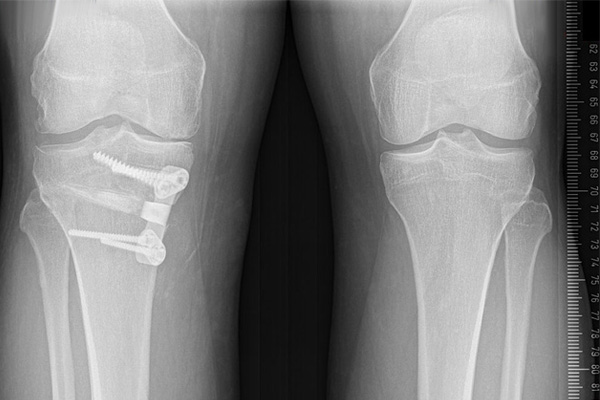

Total Knee Replacement

High Tibial Osteotomy

Trauma & fracture fixation